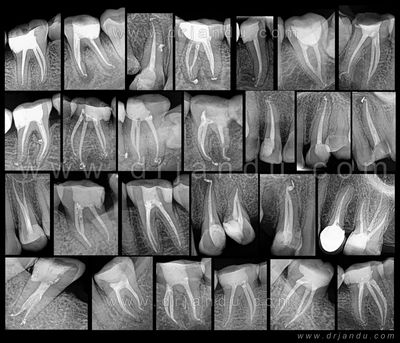

Root canal treatment is a dental procedure to remove inflamed or infected pulp on the inside of the tooth which is then carefully cleaned and disinfected, then filled and sealed. Root canal treatment is designed to eliminate bacteria from the infected root canal, prevent reinfection of the tooth and save the natural tooth.

Root canals are needed for a cracked tooth from injury or genetics, a deep cavity, or issues from a previous filling. Patients generally need a root canal when they notice their teeth are sensitive, particularly to hot and cold sensations.